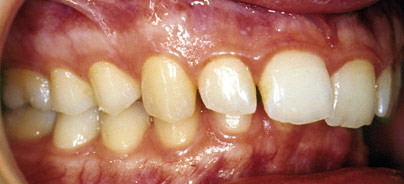

Die intraoralen Fotos (Abb. 2a–c) bestätigen und ergänzen diese Befunde hinsichtlich der sagittalen und vertikalen Disharmonie:

• distale Okklusionsverhältnisse

• tiefer Biss mit Einbiss in die Gaumenschleimhaut

• Hochstand der Unterkieferfront

• verstärkte Spee’sche Kurve.